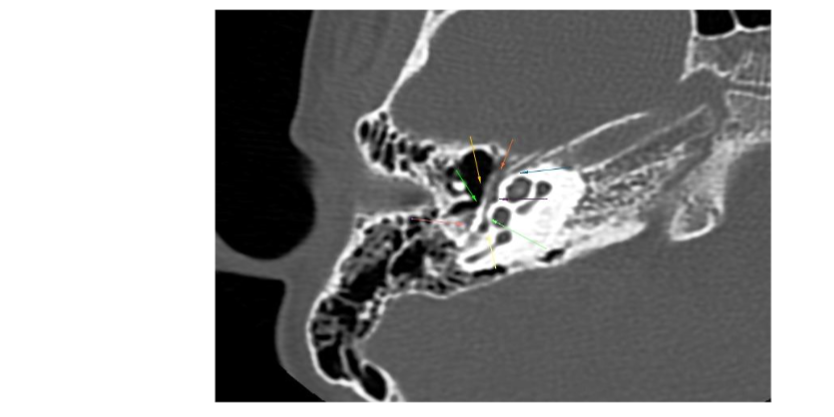

Otoendoscopy and diagnostic nasal endoscopy were normal. High resolution computed tomography (HRCT) of temporal bone showed agenesis of right stapes and dysplastic left stapes with aberrant course of facial nerve (Fig. 3, 4 & 5).

Fig.3. HRCT temporal bone – Coronal section left side showing facial nerve escaping the facial canal

Fig.4. HRCT temporal bone – coronal section left side showing only ossicular status

Fig.5. HRCT temporal bone – left side axial section showing facial nerve escaping through facial canal and coursing the promontory, through the deformed stapes

A sound radiological knowledge with study of the HRCT on the console helps in being prepared for the surgery, which may be beneficial in correcting the deformity benefitting the patient. The principal role of the radiologist in case of exploratory tympanotomy is to guide the surgeon by predicting difficulties which may be encountered during surgery. High resolution computed tomography (HRCT) of the temporal bone is the investigation of choice before surgery, but it is not performed on a routine basis for uncomplicated cases. In a study, Zeifer et al. reported that HRCT enables preoperative diagnosis of anomalous course of the facial nerve as well as absence of the oval window. This is likely due to advancements in CT imaging, allowing high spatial resolution and image quality.[10]